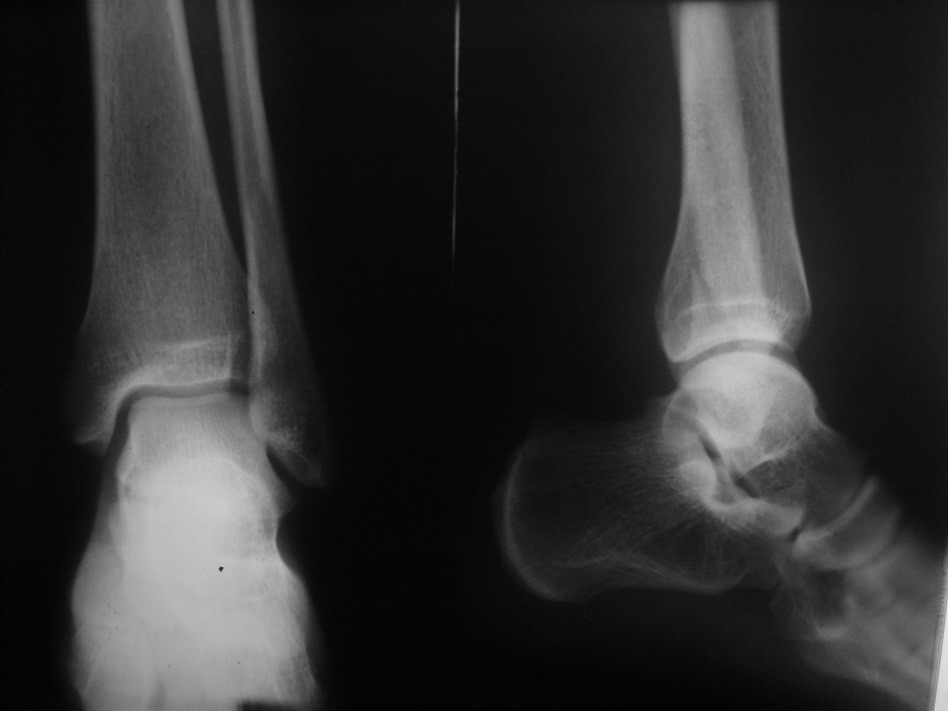

患者 男26岁 左胫腓骨扭伤

1、外踝骨折。

2、腓骨下端内生骨瘤,即骨岛。

支持外踝斜形骨折,腓骨骨岛。

支持  左侧外踝骨折,左腓骨中下段骨岛。